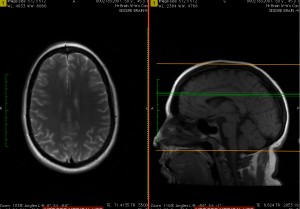

Magnetic resonance imaging (MRI) is the topic of discussion.

“Magnetic resonance imaging has revolutionized the diagnosis and treatment of a broad spectrum of medical conditions,” Mobley said. “Since its clinical debut in the 1980s, it has evolved to provide a level of anatomical detail not possible with any other imaging modality, all without the focus of an ultrasound probe or the directionality of an X-ray beam.”

“The fundamental principles at work in MRI include quantum physics, spinning tops, flipping magnets and simple patterns of bright and dark,” he said. “The aim of this talk is to remove some of the mystery of how the manipulation of the weakest magnets in the atom leads to the MR image and to look at emerging medical treatments enabled by MRI.”